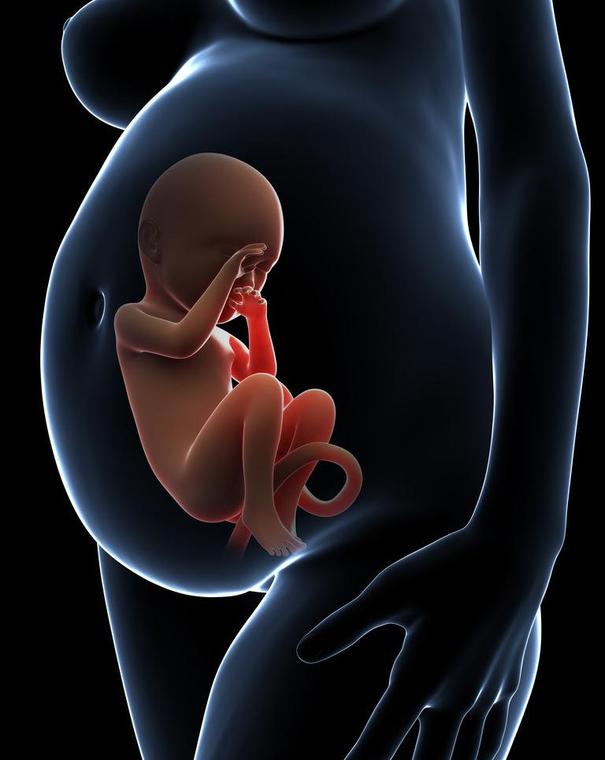

现在随着医学的发达,四维彩超基本已经普及,每个妈妈都希望生下来的宝宝是健康的,那么你知道四维彩超到底是检查了哪些项目呢?这些检查有没有必要呢?下面请让我用图片展示给大家看看。

四维彩超除了能让准父母提前看到宝宝在妈妈肚子里的活动情况,最主要的功能还在于对胎儿进行各种检查,及早发现胎儿生长中出现的问题 ,另外,四维彩超的图象显示比传统B超更清晰、更准确, 能够多方位、多角度地视察宫内胎儿的生长发育情况,为早期诊断胎儿先天性体表畸形和先天性心脏疾病提供准确的科学依据。因此,为了孕妇和胎儿的健康,产检选择做四维彩超检查非常有必要。WX(艾的秘密)